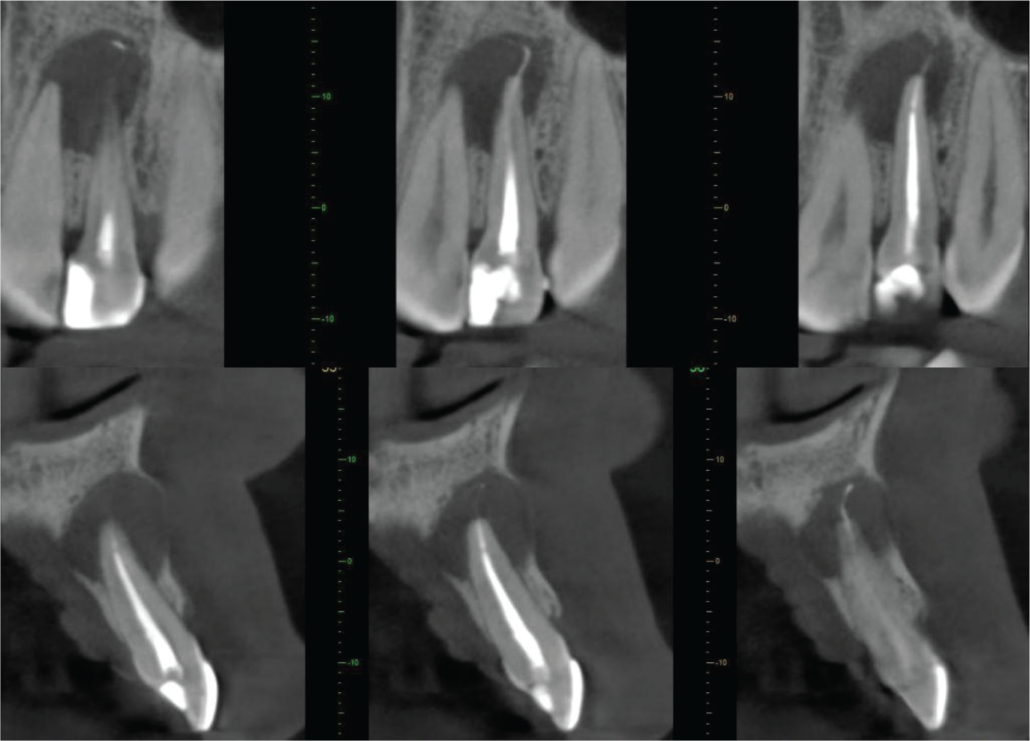

The UL2 is root-filled. The filling material extends to the apex, with extrusion of a strand of sealer or a very thin gutta percha point for 4mm beyond the apex into a well-defined ovoid radiolucency, about 10mm in diameter. The lesion extends to the palatal and labial cortices, which are both thinned and probably perforated in places. There is slight expansion of the labial cortex (image 2).

Cross-sections of UL2